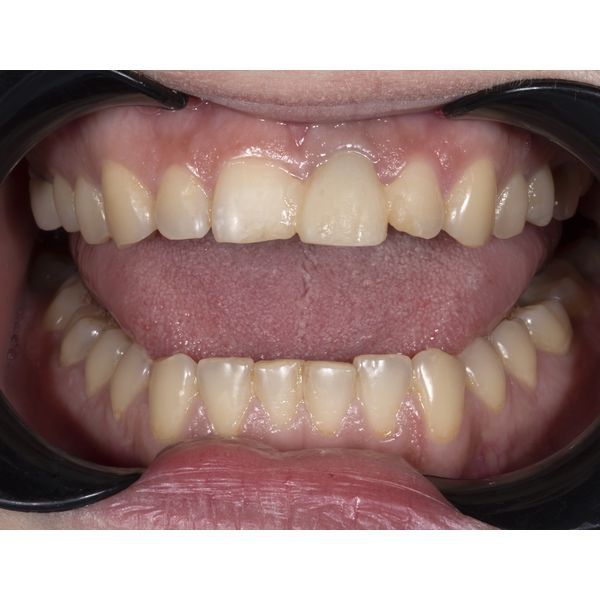

Когда имплант в кости стабилизировался, выполнили рентгенологическое исследование, чтобы оценить его приживаемость и затем провести протезированием зуба. Также предварительно отсканировали верхнюю челюсть и спроектировали будущую улыбку, далее выбрали конструкцию: циркониевую покрывную коронку с облицовкой на индивидуальном абатменте. Также провели художественную реставрацию сколотых центральных зубов с учётом заранее смоделированной улыбки пациентки.

Девушке установили имплантат и реставрировали сколотые передние зубы. Таким образом восстановили эстетику и функцию центральных резцов.